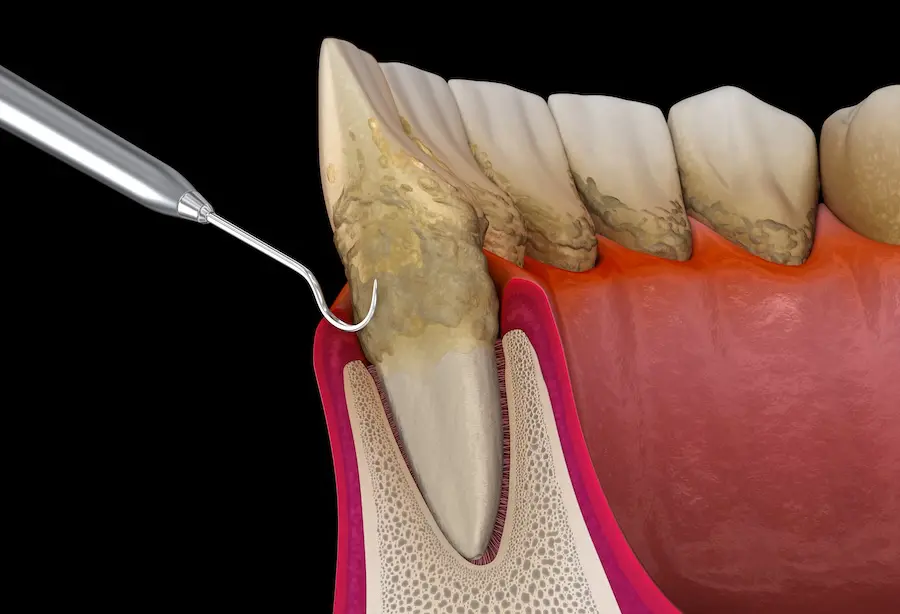

Gum Disease Treatment (Periodontal Therapy)

At Podder Dental Clinic, we offer comprehensive gum disease treatment, also known as periodontal therapy, to restore and maintain healthy gums. Gum disease, if left untreated, can lead to tooth loss and impact your overall health. Our approach includes deep cleaning procedures like scaling and root planing to remove plaque and tartar buildup below the gum line, helping to reduce inflammation and prevent further damage. In more advanced cases, we may recommend additional treatments or maintenance programs tailored to your needs with gentle care and advanced techniques.